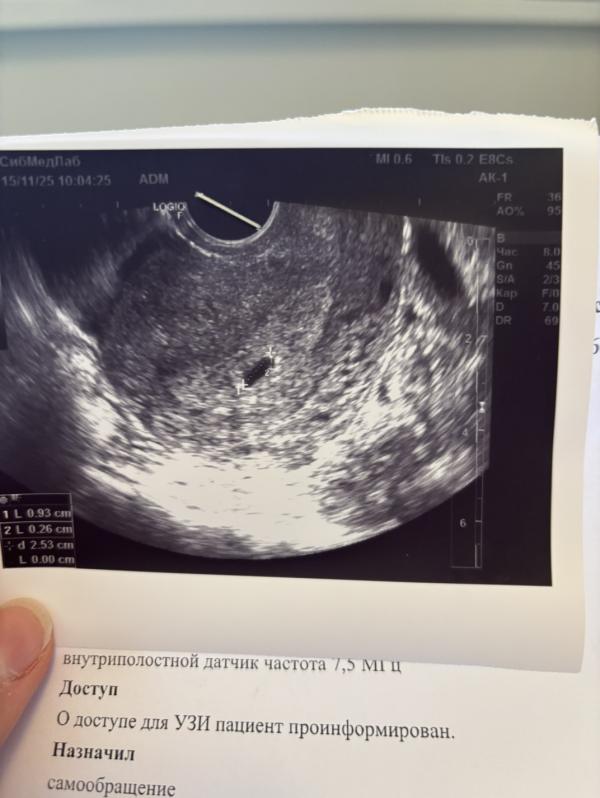

Сходила на узи на 5 неделях и 1 дне. Подтвердили, что беременность маточная. Диаметр плодного яйца 9,3 мм и диаметр желтого мешка 2,6 мм.